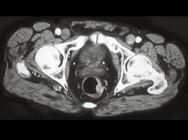

问题 男性,41岁,血便,肛诊触及左侧直肠壁一质硬小结节,结合CT所见应考虑为()

选项 A.直肠腺瘤 B.直肠癌 C.直肠息肉 D.直肠转移瘤 E.直肠间质瘤

答案 B